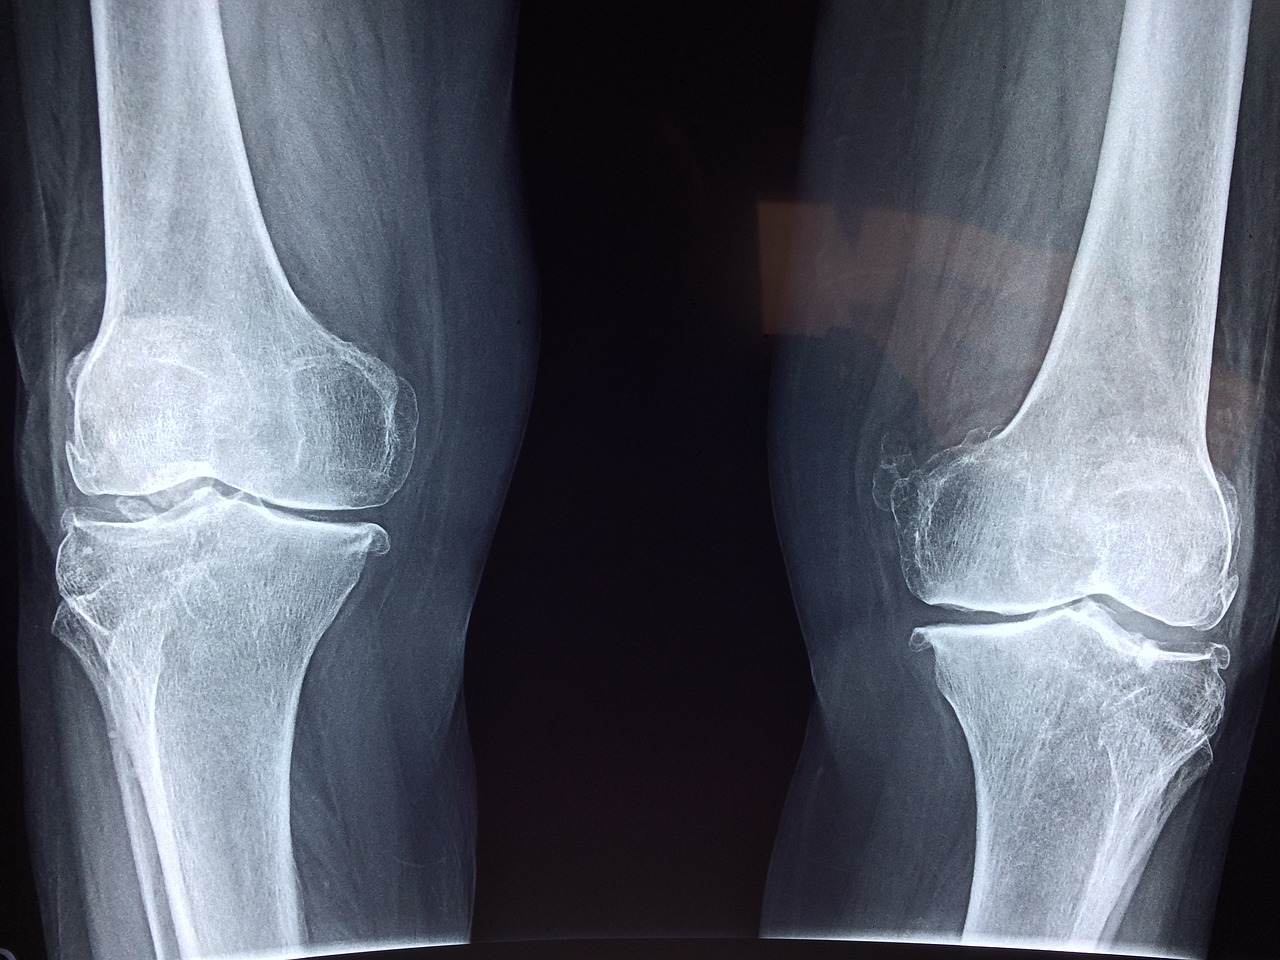

무릎 인공관절 수술 후 스타킹 착용 기간은 보통 2주에서 6주까지로 권장됩니다. 다만 정확한 기간은 환자의 회복 속도, 혈전 위험도, 활동량 등에 따라 달라질 수 있습니다.

● 일반적으로는 수술 후 2주간은 반드시 착용하며, 의사 지시에 따라 점차 착용 시간을 줄여나가는 방식이 효과적입니다.

● 부기가 심하거나 정맥류 병력이 있는 경우는 4~6주까지 착용하는 경우도 많습니다.